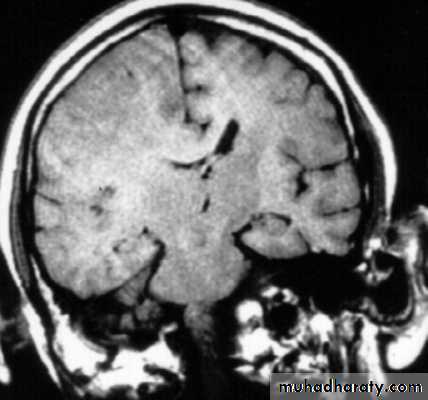

1. Diffuse Axonal Injury

Prolonged post-traumatic state in which there is loss of consciousness from the time of injury that continues beyond 6 hours.

Occurs as a result of mechanical shearing at the grey-white matter interface.

This causes disruption and tearing of axons, myelin sheaths and blood capillaries.

Severity can range from mild damage with confusion to coma and even death.